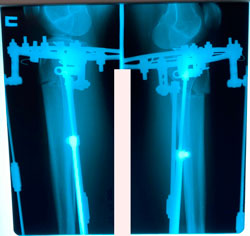

перед крутками

image-17-10-20-09-56-2.jpg